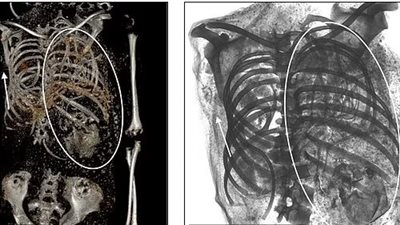

توأم أحدهما في الصدر.. العثور على رأس طفل بحوض أم مصرية ماتت أثناء الولادة منذ 1500 عام